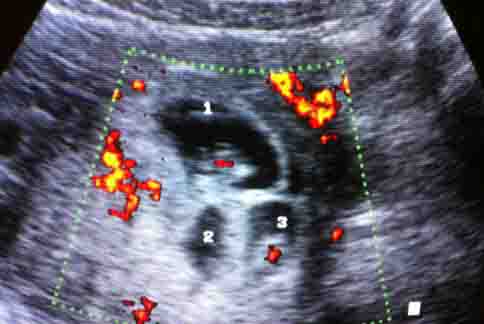

把愛子生回來 母親節前夕產下龍鳳胎

【華人健康網 記者黃曼瑩/台北報導】 2012年5月9日 12:57http://www.top1health.com/Article/4832

一名現年48歲的婦人,在多年前的母親節前夕,在一次...